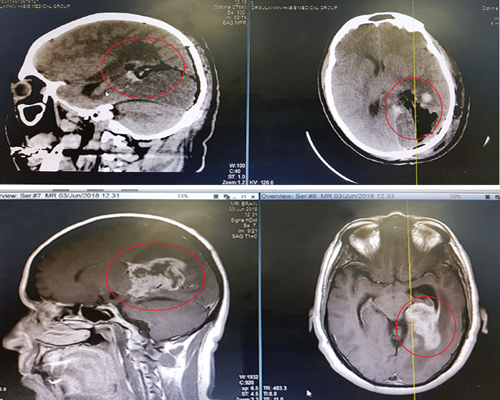

إلى ذلك قال الدكتور ناجي المسعود طبيب جراحة المخ والأعصاب الحاصل على الزمالة الألمانية رئيس الفريق الجراحي المعالج: «المريض عانى كثيرًا من المرض لبضع سنوات وحاول العلاج في أكثر من مستشفى ولكن دون جدوى، وفور وصوله للمستشفى تم إخضاعه للفحوصات المخبرية والشعاعية عن طريق التصوير المقطعي C.T Scan والرنين المغناطيسيM.R.I، ومن ثم تحويله للعناية المركزة. حيث أوضحت النتائج تمركز ورم كبير في المنطقة اليسرى في الدماغ الأمر الذي يفسر حدوث الأعراض السابق ذكرها».

وأضاف: «الأشعة أوضحت أيضًا خطورة مكان الورم نتيجة قربه من مراكز الإدراك والحركة والنظر والوعي بالدماغ. كما أن كبر حجم الورم أدى إلى الضغط على شبكة الأوردة المركزية في المخ. الأمر الذي يحتاج معه إلى دراسة وعناية شديدة لإجراء عملية استئصال الورم لأكثر أماكن الجسم حساسية».